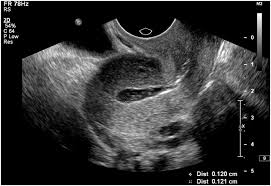

2. Endometrial Pattern

• Ideal pattern: Triple-line (trilaminar) appearance on ultrasound before embryo transfer.

• This pattern indicates good estrogen responsiveness and better chances of implantation.

• Non-ideal pattern: Homogeneous (hyperechoic) lining may indicate suboptimal implantation conditions.